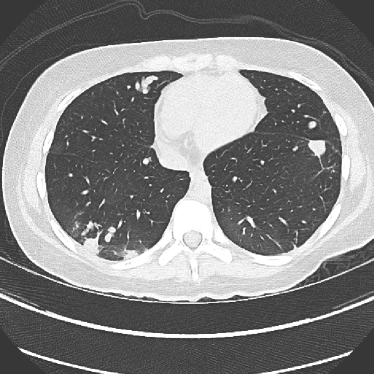

Figure 14: Qualitative clinical results from a thoracic CT staging dataset for a 12-year-old with osteosarcoma with pulmonary metastases. The clinical standard hybrid IR is shown on the left and JENG is on the right. (a) The clinical standard hybrid IR in lung window with a window center of -600 HU and a window width of 1500 HU. (b) JENG at a resolution comparable to the clinical standard, but with less noise and fewer artifacts. (c) The clinical standard hybrid IR in soft tissue window with a window center of 55 HU and a window width of 440 HU. A metastatic lung cancer nodule can be found in the left upper lobe. (d) JENG in soft tissue window at a comparable resolution, but with less noise and fewer artifacts. Note that JENG is not fully corrected for beam hardening artifacts.

V.B. Clinical Cases

None of the spatial resolution and artifact reduction advantages would hold unless JENG shows image quality improvement over the clinical standard method on patient datasets. To do so, we evaluated JENG on 5 thoracic and 3 abdominal CT scans and all scans used the same parameter settings as those for the ACR phantom scan, except that the tube current and the pitch is modulated individually for each patient. The exact experiment setup was discussed in Sec. IV.. For a fair image quality comparison, we matched the resolution of JENG and the clinical standard hybrid IR and studied their image noise and artifacts.